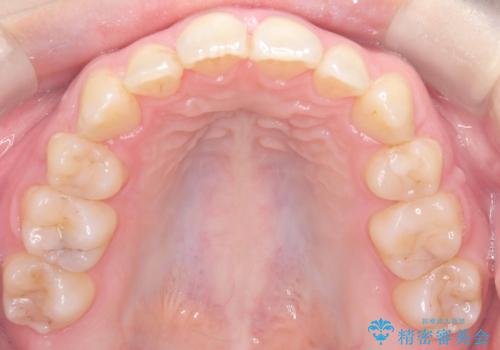

- 「歯のデコボコ、八重歯、口ボコが気になる」を主訴に来院された患者様です。

上下左右4番(4本)の歯を抜歯しワイヤー矯正で治療を行いました。

計4本の抜歯を行い、歯のデコボコと口元がすっきりし、大変ご満足していただけました。